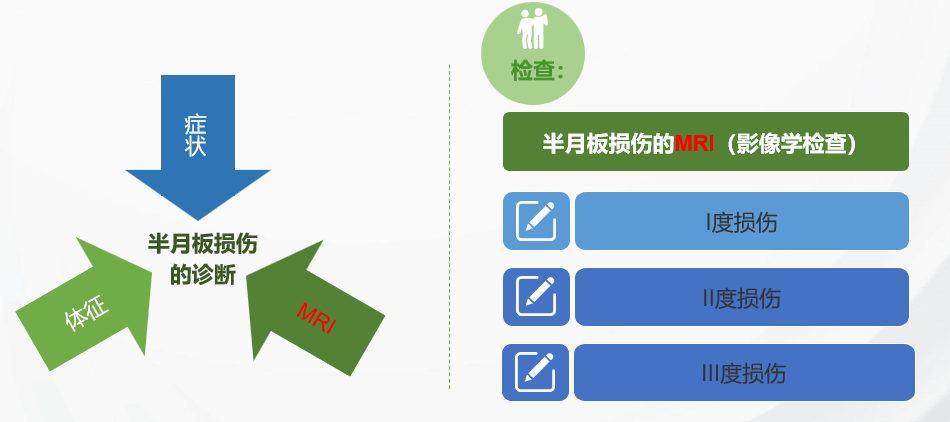

【半月板损伤的诊断】

诊断之一:症状

诊断之二:体征

诊断之三:MRI

半月板损伤的三类信号